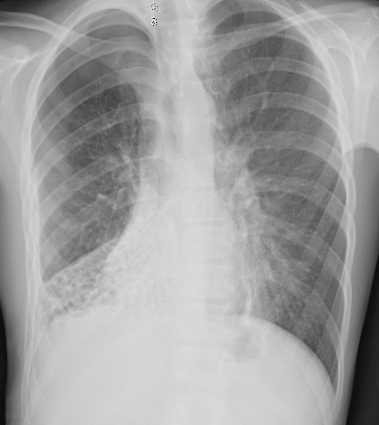

Foi solicitada radiografia do tórax em AP e perfil.

Diante das imagens, qual achado pode ser responsável pela piora súbita na dispneia?

BPequeno pneumotórax à direita

DPneumonia em base direita